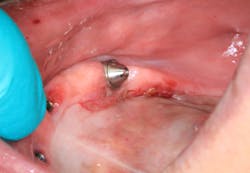

The unknown etiology of the lesion automatically put it into a category of high-risk leukoplakia, especially since it had just recently manifested and there had been a history of previous biopsy to the area that was diagnosed as precancerous tissue. The patient was seen in my office for prosthesis removal and then referred to an oral surgeon, where she had an excisional biopsy under local anesthesia (figures 5 and 6). The patient's prosthesis was adjusted and appropriate follow-up care was put in place.